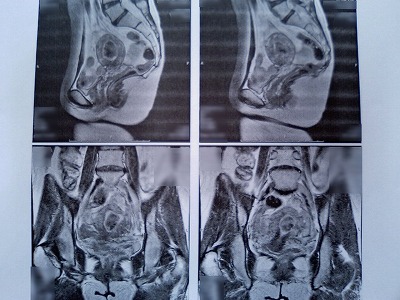

●子宮動脈塞栓術 3ヶ月検診

●2005年 4月11日 MRI画像

筋腫の大きさ→だいたい4cmの大きさと言われました。

(ヘモグロビン→7.5g/dl)

●2005年 9月 1日 MRI画像

筋腫の大きさ→画像写真の下にある1メモリが1cmと言う事で、2cm位でしょうか?

(ヘモグロビン→12g/dl)

筋腫の色も黒くなっており、UAEは成功との事でした。

この筋腫が大きくなる事はなく、これから時間をかけて小さくなっていくとの事です。